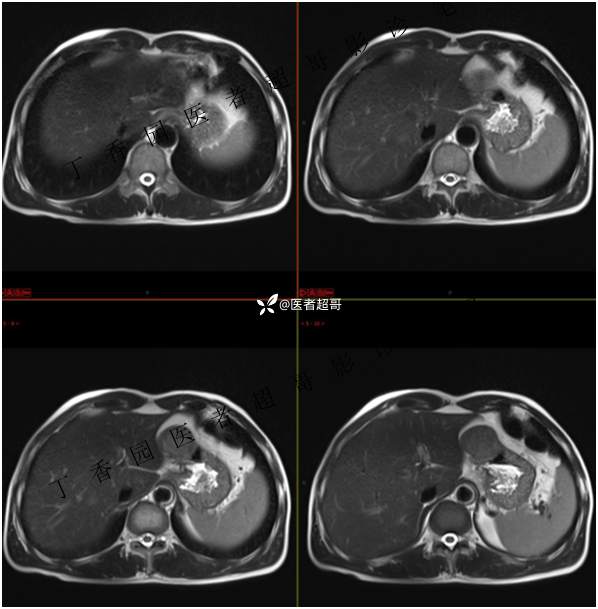

肝胃间隙肿瘤,间质瘤?平滑肌瘤?还是鞘瘤?有结果,请分析!

现病史:患者于3天前查体行肝胆脾胰肾彩超示肝内实性占位,无恶心、呕吐,无发热、寒战,无腹胀、腹泻,进一步于医院行上腹部CT增强示:肝胃交界处肿块。未行特殊治疗。今患者为求进一步治疗,来我院就诊,门诊以“肝占位性病变”收入院。患者自发病以来,神志清,精神可,饮食睡眠可,二便可,体重近期未见明显变化。